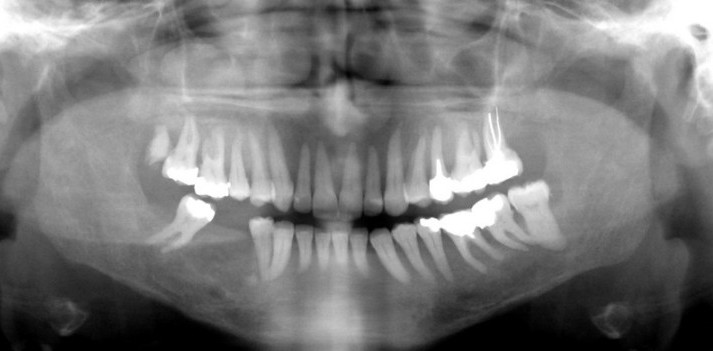

- Παρατηρείται λέπτυνση των συμπαγών πετάλων και οστική αραίωση της μυελώδους μοίρας με αποτέλεσμα την ακτινογραφική εικόνα “τριμμένου γυαλιού”.

- Απώλεια της lamina dura. Λέπτυνση του κάτω χείλους της κάτω γνάθου.

- Σε προχωρημένο στάδιο, μπορεί να εμφανιστούν εντοπισμένες διαυγάσεις με σαφή όρια (καστανόχρωμοι όγκοι- brown tumors).